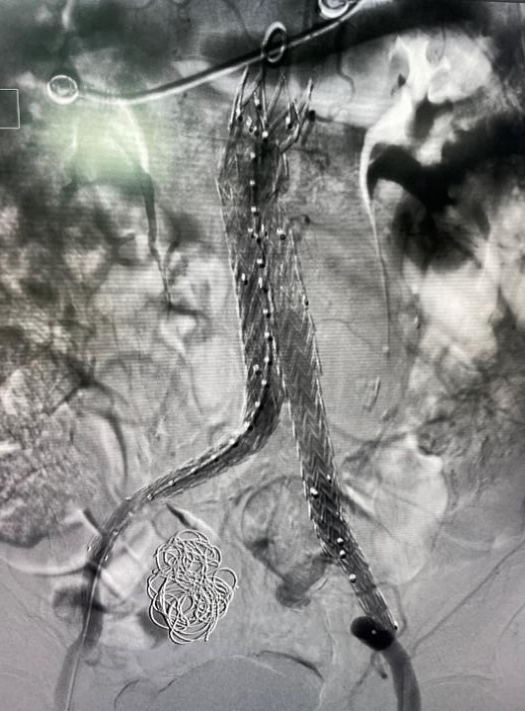

腹主動(dòng)脈動(dòng)脈瘤腔內(nèi)隔絕術(shù)

2月28日,神經(jīng)內(nèi)科介入團(tuán)隊(duì)在西安交通大學(xué)第一附屬醫(yī)院血管外科蔡惠副主任的指導(dǎo)下成功為李伯實(shí)施了“右側(cè)髂動(dòng)脈瘤栓塞+腹主動(dòng)脈瘤腔內(nèi)隔絕術(shù)”,手術(shù)歷時(shí)2小時(shí)順利完成。

術(shù)后造影圖

術(shù)后,李伯再次造影提示支架貼合良好,且未發(fā)現(xiàn)內(nèi)漏、周?chē)K器血管閉塞等并發(fā)癥。次日李伯就能下床活動(dòng),行走自如。目前,西電集團(tuán)醫(yī)院神經(jīng)內(nèi)科介入團(tuán)隊(duì)已成功為四名患者“拆除”腹腔“炸彈”。